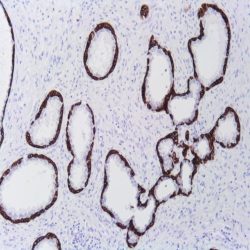

| Clone | Clone EP300 |

| REF | PSV-IHI0360 |

| Dilution | 1:50 |

| Staining | Cytoplasm |

| Control tissue | Tissue section from chromophobe carcinoma of the kidney |

| Isotype | IgG |

| Species of origin | Rabbit |